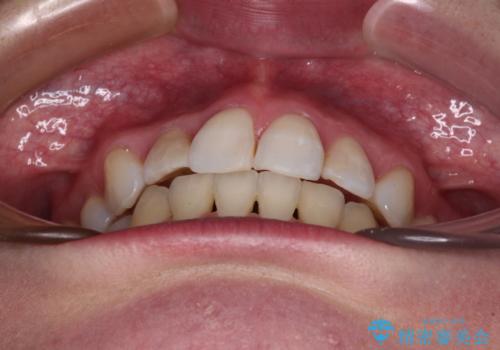

- 前歯のデコボコと上顎の前突感による口の閉じにくさを気にして来院された患者様です。

目立たない装置を希望されたので、上顎が裏側装置のハーフリンガルを選択し、上下左右の小臼歯(計4歯)を抜歯して矯正治療を行うこととしました。

期間はかかったものの、口元の張り出し感や歯のデコボコが解消され、患者様には大変満足していただけました。